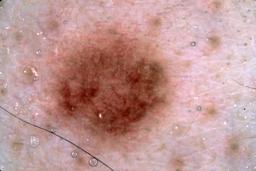

{

"age_approx": 35,

"anatom_site_general": "posterior torso",

"concomitant_biopsy": true,

"dermoscopic_type": "contact non-polarized",

"diagnosis_1": "Benign",

"diagnosis_2": "Benign melanocytic proliferations",

"diagnosis_3": "Nevus",

"diagnosis_4": "Nevus, Congenital",

"diagnosis_confirm_type": "histopathology",

"image_type": "dermoscopic",

"lesion_id": "IL_5611413",

"melanocytic": true,

"patient_id": "IP_2466920",

"sex": "female"

}